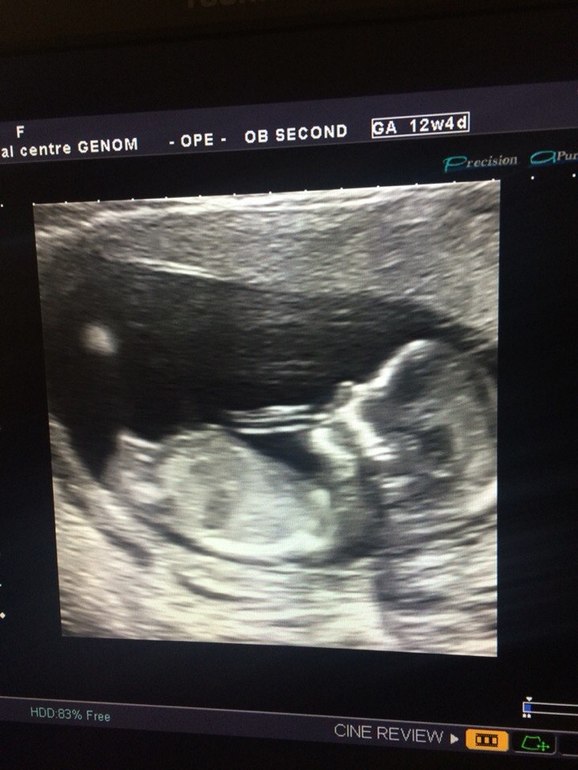

1 скрининг на 12,4 неделе

Ктр 64 мм. Сказали размеры носика, воротникового отдела, бедра, окружность головы. Показали сердце, мозг, желудок. Включили послушать удары сердца, сказали, что кровообращение в норме. Показали, как шевелится)) прикольно так)) аж слезу пустила)) у меня двурогая матка, сказали, что ему там не тесно)))

Здорово, мы по размерам побольше, КТР -7.1 см, воротник — 0.9, а носовая косточка аж 2.7 мм)), но мне и срок поставили по узи 13.5 нед, хотя по мес. всего 12. Из неприятного — тонус и полное предлежание плаценты, но это еще будет меняться ). Да впечатления незабываемые, прямо как на свидание сходила в 15 лет )) улыбаюсь до сих пор ))